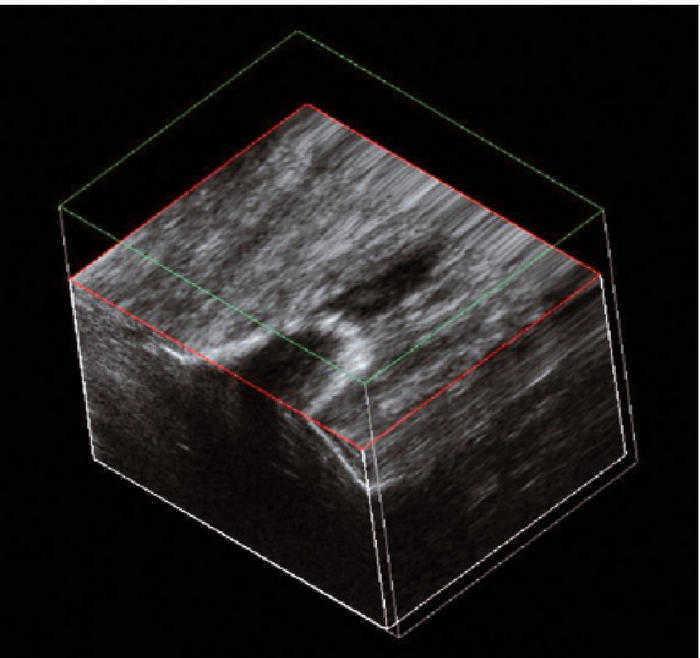

Este paciente presentaba dolor rotuliano crónico en relación con el ejercicio físico desde hacía varios años. El estudio longitudinal realizado con ambos equipos (E-A y E-B) permite observar una gran calcificación que invade la porción proximal del tendón31-34. Dicha calcificación produce una sombra acústica posterior (fig. 5A) visualizable de modo similar con ambos equipos (fig. 5B), aunque con el equipo E-B se observa la presencia de una zona hipoecoica amplia, próxima a la calcificación. Además, el E-B permite el estudio en 3D (fig. 6).

Figura 6 La imagen en 3 dimensiones del equipo E-B se obtiene mediante un barrido transversal con acumulación de imágenes sucesivas que permiten observar la calcificación en todos los planos.

El caso de la tendinosis calcificante del tendón rotuliano (caso 4), las imágenes obtenidas con ambos equipos (E-A y E-B) demuestran con nitidez la presencia de una gran calcificación que surge del polo inferior de la patela. Sin embargo, la utilización del sistema 3D en el equipo E-B supone una ventaja, pues permite visualizar en 3D la disposición de la calcificación29,30-32,36.